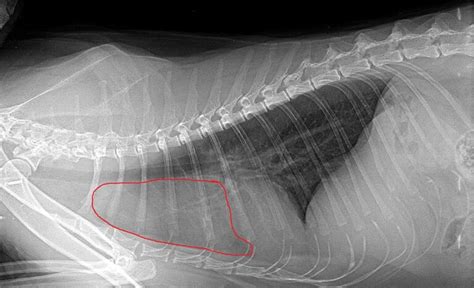

Diagnoza ankilozirajočega spondilitisa temelji na bolezenski sliki, ker bolezni z nekaterimi laboratorijskimi preiskavami ni mogoče zanesljivo odkriti. Diagnoza temelji na značilnem vzorcu bolezenskih znakov in rentgenskih slikah hrbtenice in velikih sklepov, na katerih so vidne erozije v sklepu med hrbtenico in medenico (sakroiliakalnem sklepu) in zakostenele povezave med vretenci, zaradi katerih je hrbtenica otrdela. Pri kliničnem pregledu na začetku bolezni zdravnik največkrat ne ugotovi bolezenskih sprememb. Pri napredovali bolezni pa so opazni izravnana krivina ledvene hrbtenice in poudarjena krivina prsne hrbtenice, zmanjšana gibljivost hrbtenice v vse tri smeri ter zmanjšana razteznost prsnega koša. Na začetku bolezni lahko postavitev diagnoze predstavlja velik izziv, saj ni značilnih in občutljivih testov za to bolezen. Klinični pregled na začetku bolezni običajno ne pokaže odstopanj od normale.